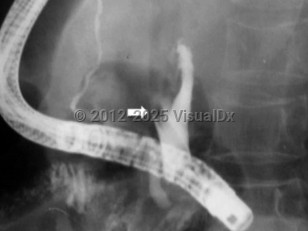

Ascariasis

While currently uncommon in the United States, infection with A lumbricoides (ascariasis) is still prevalent in developing countries. Risk factors include warm and humid climates, poor sanitation, and poor hygiene. Ascaris lumbricoides is thought to cause a major burden of disease worldwide due to acquired nutritional deficiencies (although some studies question whether the degree of nutritional deficiency is a significant factor in the development of disease). However, it is difficult to isolate the burden of disease of A lumbricoides specifically, since many individuals are coinfected with other parasites such as hookworms and whipworms. Young children (namely, preschool and school-aged) tend to carry higher numbers of parasites compared with adults, leading to growth retardation, impaired memory, and worsened cognition.